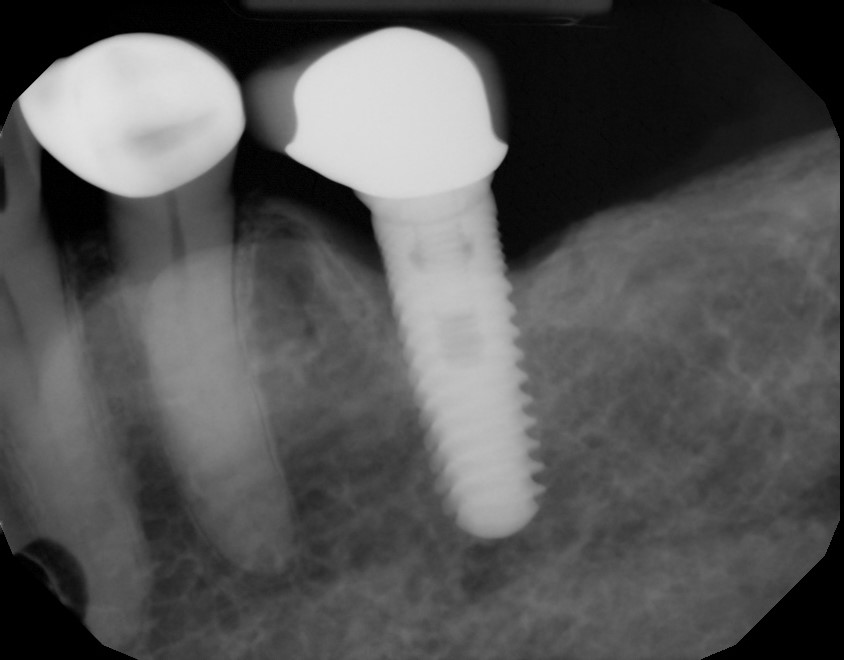

This mouth had recession on just one tooth with very little bone to support the tooth. The area needed support and thickness. The tissue was placed and the area now has thicker tissue to withstand the forces that the patient needs to place on it.